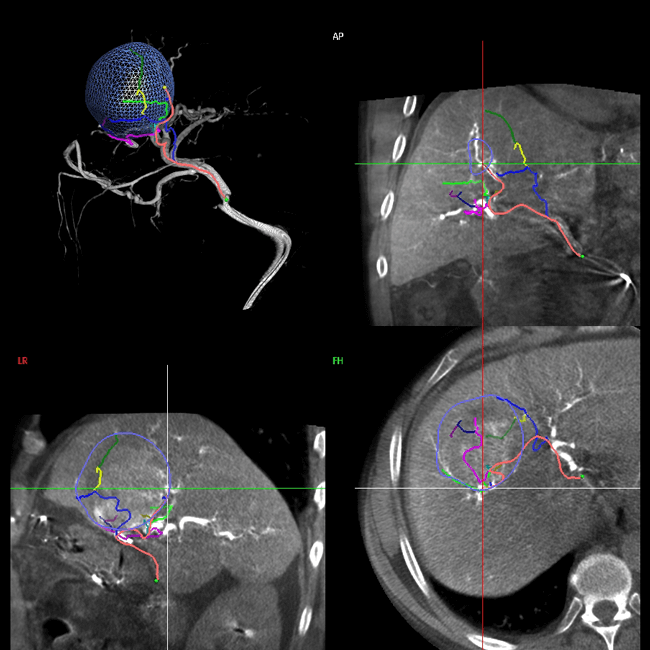

Sistema Emboguide: identifica las ramas tumorales para la embolización de tumores, con ahorro de medio de contraste u dosis de radiación.

Fusión de imagen 2D y 3D, funciona para realizar intervenciones en la aorta abdominal.

Adquisición de bajo contraste para hígado, abdomen y de arteria prostática.